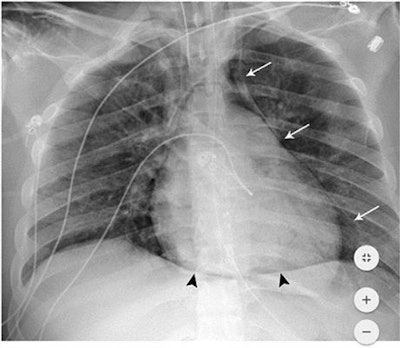

The NYU Langone researchers had observed a higher incidence of barotrauma in patients with COVID-19 and sought to determine if the disease was a risk factor for these events, which include pneumothorax, pneumomediastinum, pneumopericardium, and subcutaneous emphysema.

Patients with COVID-19 who require invasive mechanical ventilation are more likely to experience barotrauma such as pneumothorax and pneumomediastinum than those without the disease, according to research published online July 2 in Radiology. And younger patients with COVID-19 were particularly at risk for these serious events.